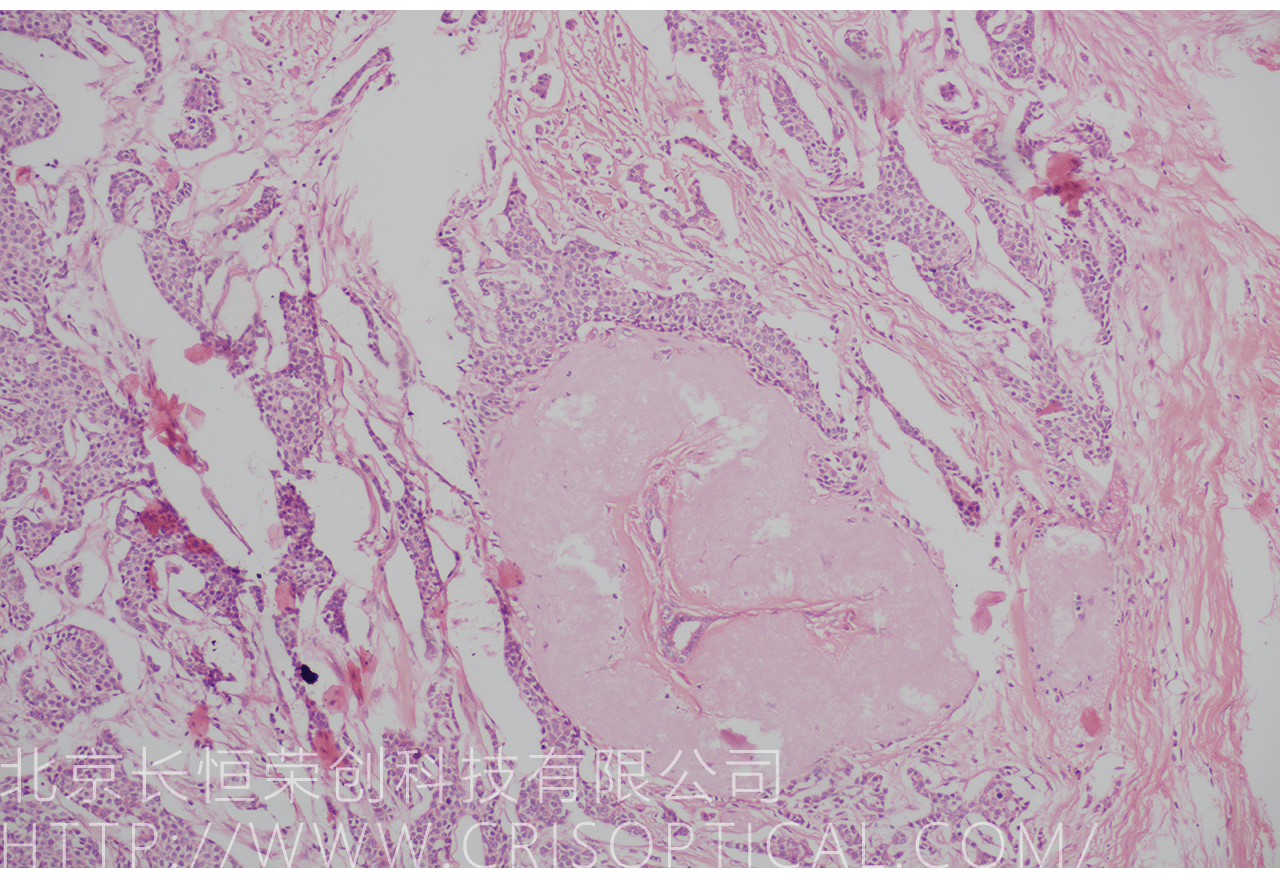

病理切片觀察是一種重要的醫(yī)學(xué)實(shí)踐,通過對(duì)組織和細(xì)胞切片的

顯微鏡觀察,幫助醫(yī)生診斷疾病、評(píng)估病情和制定治療方案。病理切片觀察在

臨床醫(yī)學(xué)、癌癥診斷、外科手術(shù)和疾病研究中發(fā)揮著關(guān)鍵作用。

腫瘤診斷:對(duì)癌癥和其他腫瘤的病理切片觀察是確定腫瘤類型、分級(jí)和分期的關(guān)鍵步驟。醫(yī)生通過觀察組織樣本中的細(xì)胞形態(tài)、核形狀、分裂活性和其他特征,可以識(shí)別腫瘤的類型,幫助決定治療方法。

外科手術(shù)指導(dǎo):在外科手術(shù)中,醫(yī)生可能會(huì)采集組織標(biāo)本,然后由病理學(xué)家進(jìn)行切片制備和觀察。手術(shù)中的快速冰凍切片術(shù)可以提供實(shí)時(shí)的病理診斷,幫助外科醫(yī)生確定手術(shù)范圍、移除腫瘤或其他異常組織。